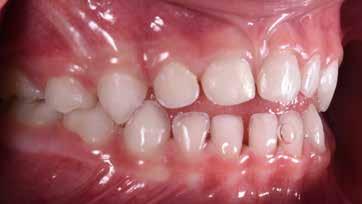

Presentazione del caso > F.V, bambino di cinque anni, presenta una malocclusione di II Classe scheletrica, III Classe dentale molare e canina destra e sinistra, morso inverso anteriore. Le arcate dentali mostrano usura degli elementi dentari anteriori a causa dell’occlusione patologica. Le linee mediane, superiore ed inferiore, sono centrate; il frenulo labiale superiore patologico per un’eccessiva estensione inter-incisale.

Il piano di trattamento prevede l’utilizzo di un dispositivo elastodontico di III Classe, da portare per due ore diurne e tutte le notti in modo passivo, senza effettuare alcun esercizio, al fine di ripristinare una relazione molare e canina bilaterale di I Classe ed il corretto avanzamento maxillare e inibire l’eccessiva crescita mandibolare. È possibile ottenere il risultato in pochissimi mesi di terapia, essendo la crescita del paziente molto attiva.

Dall’esame clinico si evince la III Classe dentale, l’inversione anteriore e l’over-jet negativo.